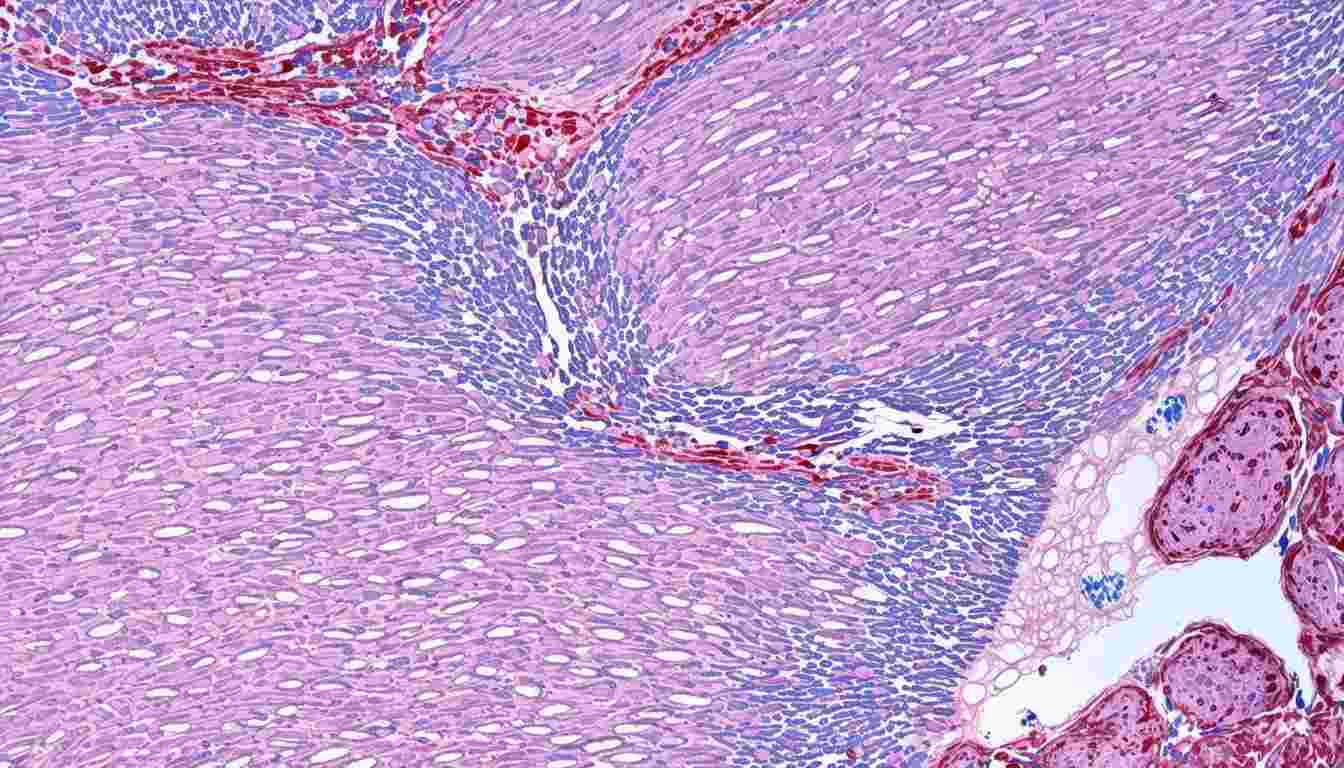

Loose connective tissue is a vital component of the human body, providing structural support, immune defense, and metabolic exchange. It consists of an extracellular matrix composed of fibers, ground substance, and various cell types.

Composition

- Fibers: Collagen (strength), elastin (elasticity), and reticular fibers (support)

- Ground Substance: A gel-like material that facilitates nutrient diffusion

- Cells: Fibroblasts (secrete matrix), mast cells (immune response), macrophages (phagocytosis), and adipocytes (energy storage)

Locations in the Body

Loose connective tissue is widely distributed across the body, filling spaces between organs, under epithelial layers, and surrounding blood vessels. Examples include:

- Areolar Tissue: Found beneath the skin, supporting capillary networks

- Adipose Tissue: Stores fat and insulates the body

- Reticular Tissue: Forms the framework of lymphoid organs